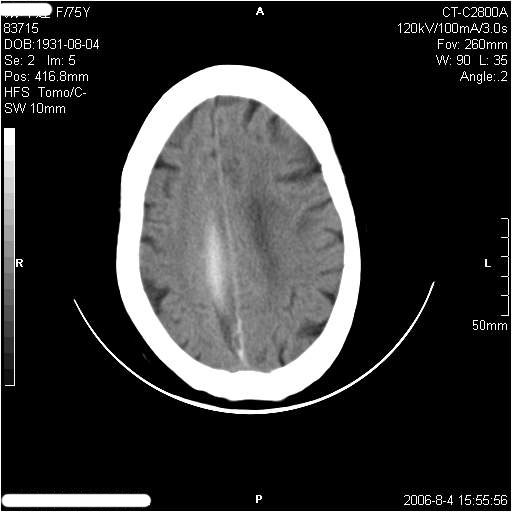

左侧偏瘫3天.

1纵裂硬膜下血肿,2双基底节脑软化灶.

1、纵裂硬膜下血肿,2、右侧室前角旁梗塞;3、双基底节脑软化灶.

镰旁慢性硬膜下出血?双侧多发腔梗。

有摔倒外伤史,另看右侧灰白质界限.

双侧基底节区多发性腔梗.引起临床症状的主要原因是右侧侧脑室旁的梗塞病灶.

应该是右侧大脑镰旁的血肿,右侧基底节区脑梗塞。

1、该患者从脑实质表现情况看应该年龄较大了,双侧基底节区多发斑片状低密度灶,侧脑室旁白质密度减低,各脑室腔扩大,脑沟裂增宽加深,以上改变符合:皮层下动脉硬化性脑病。

2、上纵裂右侧梭形条状高密度影阴,边缘模糊,周围水肿带环绕,右侧脑室受压变形,有摔倒外伤史,多考虑:纵裂硬膜下血肿。

支持纵裂硬膜下血肿,应该是慢性,或是再出血.